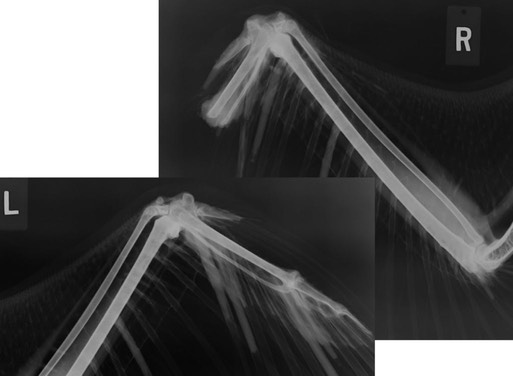

Bald Eagle 18-380

The week ended with the admission of a young Bald Eagle who somehow had severed the tip of his right wing. The very tips of his tail feathers had also been cut off. If only he could speak and tell us what had happened.